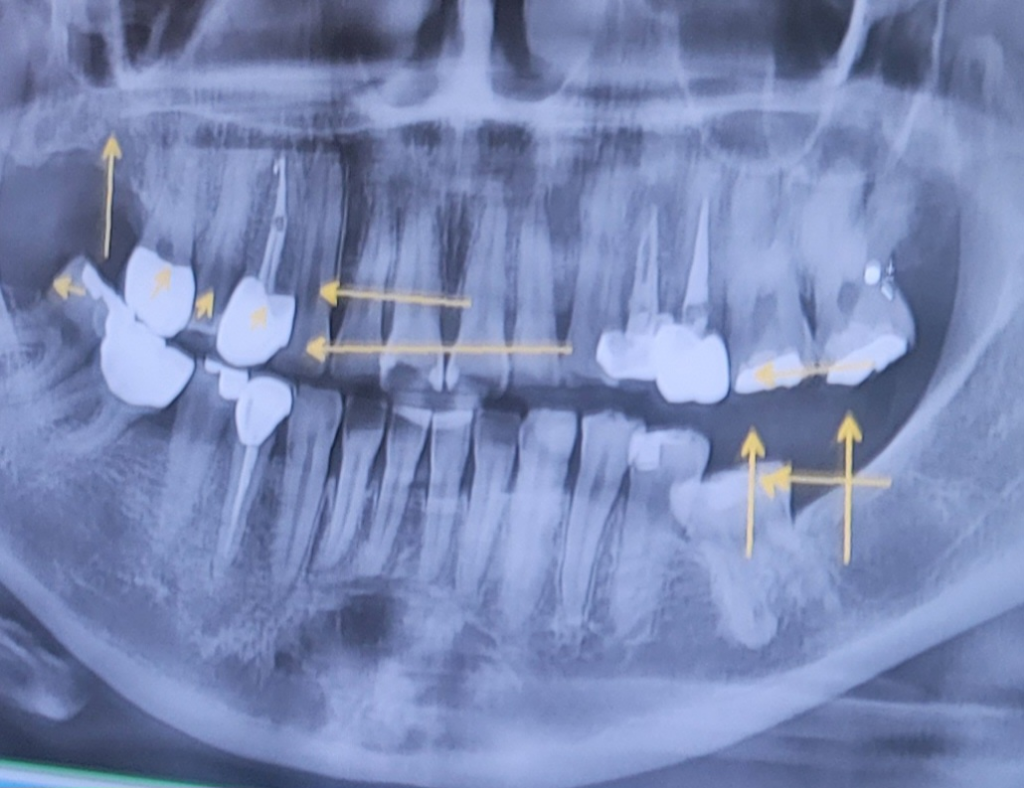

1. 왼쪽 아래 어금니의 경우 견인해서 기능이 가능할 정도로 정출시켜 쓸 수 있다면 쓰는 것이 좋습니다. 그게 힘들다면 발치를 하고 임플란트를 고려하면 되고 발치 이전에 해볼 수 있는 치료가 있다면 해보는 것도 나쁘지 않습니다.

2. 왼쪽 아래 어금니 처치가 늦어지면 왼쪽 위 어금니 2개가 점차 아래로 내려옵니다. (정출현상) 따라서 너무 늦지 않게 1~2년 내로 처치를 해주는 것이 좋습니다. 만약 처치가 늦으져서 왼쪽 위 어금니 2개가 내려온 뒤에 왼쪽 아래 부위에 대해 처치를 하고자 한다면 왼쪽 위 어금니에 대해서도 치아 높이를 조금 삭제하고 크라운을 씌우는 등의 처치가 필요할 수 있습니다.

3. 오른쪽 위 치아 상실부위의 경우 무조건 임플란트가 필요한 부위는 아니지만 확실히 임플란트를 해주면 주변 치아의 교합력에 대한 분산에 도움은 됩니다.

4. 오른쪽 아래는 사진상에서는 짤려서 사랑니가 보이지 않습니다.